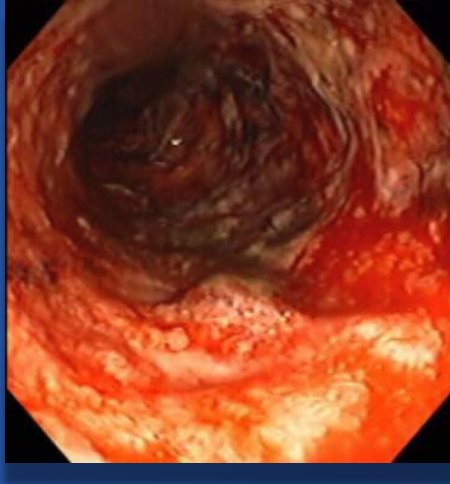

| Colonoscopy/Biopsy | Skip lesions, cobblestoning, transmural ulcers | Friable mucosa, pancolitis, submucosal ulcers, continuous lesions |